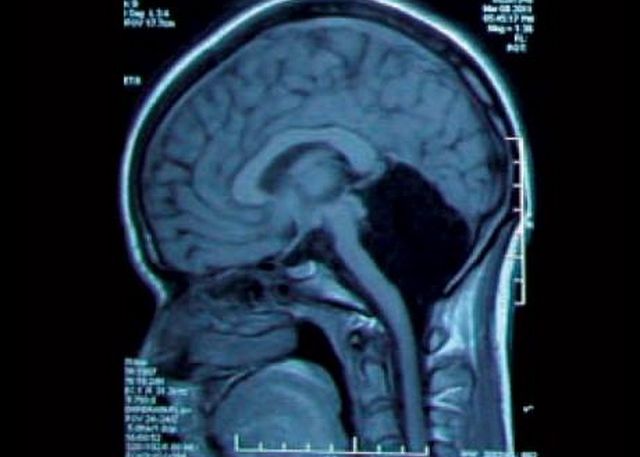

La o radiografie de rutina facuta la un spital din Provincia Shandong, China, unei tinere de 24 de ani care se plangea de greata si dureri de cap, medicii au observat ceva incredibil: femeia nu avea deloc cerebel. Cerebelul, numit si creierul mic, este zona cerebrala care controleaza echilibrul, miscarile voluntare, vorbirea si alte deprinderi motorii. Lipsa ori afectarea lui duce in mod normal la un handicap extrem de grav sau chiar la moarte.

Cu toate acestea, tanara pacienta ducea o viata normala si nu banuise nicio clipa ca sufera de o malformatie atat de grava. Ea s-a nascut practic fara cerebel, care constituie 10% din masa creierului. In locul acestuia, pacienta are un lichid cerebral, scrie publicatia Science Alert.